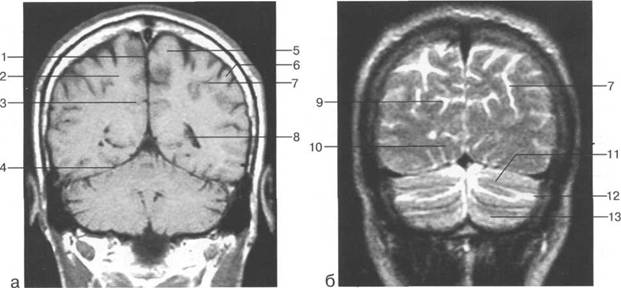

Задняя череп 13513u2010n 85;ая ямка представляет собой часть основания череп 13513u2010n 72;, ограниченную централь

Следует отметить, что в настоящее время оптимальным методом исследования структур задней череп 13513u2010n 85;ой ямки является МРТ, которая, в отличие от КТ, лишена артефактов от кост

Мозжечок заполняет практически весь объем задней череп 13513u2010n 85;ой ямки. Его поперечный раз

IV IV IV IV III IV

височная доля; 17 - полушарие мозжечка; 18 - |